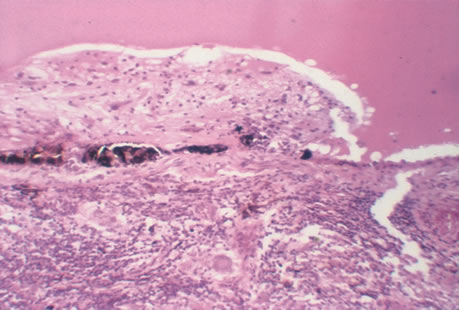

Any cell type may be infected, appearing larger than normal (cytomegalic) and demonstrating eosinophilic intranuclear “owl's eye” and smaller intracytoplasmic viral inclusion bodies, which are better seen with Giemsa or Papanicolaou's stains (Fig. 8). Histologic examination of tissue specimens, including bronchoalveolar lavage fluid and urine, may be useful for diagnosis.